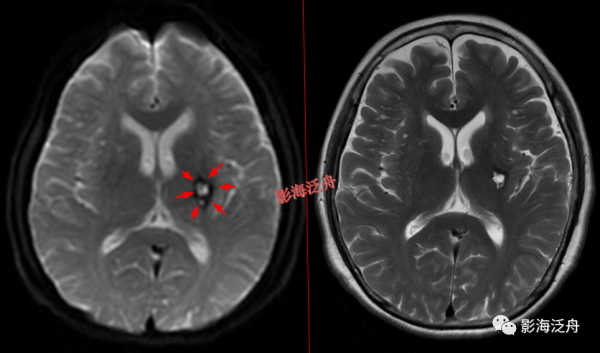

![]()

I型-基底節型:擴大VR腔隙呈對稱性分佈於雙側基底節區(紅箭),左側較大呈圓形,右側較小呈斑點狀。基底節型擴大VR腔隙好發於基底節下部,尤其是前聯合層面(黃箭所指為前聯合)。

這種不成形的多發斑點狀、細線樣異常訊號在基底節區下部也是比較常見的。